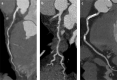

Cardiovascular imaging has significantly evolved since the turn of the century. Progress in the last two decades has been marked by advances in every modality used to image the heart, including echocardiography, cardiac magnetic resonance, cardiac CT and nuclear cardiology. There has also been a dramatic increase in hybrid and fusion modalities that leverage the unique capabilities of two imaging techniques simultaneously, as well as the incorporation of artificial intelligence and machine learning into the clinical workflow. These advances in non-invasive cardiac imaging have guided patient management and improved clinical outcomes. The technological developments of the past 20 years have also given rise to new imaging subspecialities and increased the demand for dedicated cardiac imagers who are cross-trained in multiple modalities. This state-of-the-art review summarizes the evolution of multimodality cardiac imaging in the 21st century and highlights opportunities for future innovation.